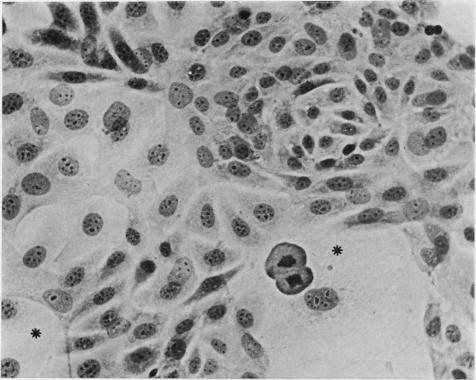

Cryostat sections and established in vitro cultures of dimethylnitrosamine(DMN)-induced renal mesenchymal tumours and monolayer cultures of transformed kidney cells derived from rats treated with a carcinogenic dose of DMN were examined by indirect immunofluorescence with human serum containing smooth muscle antibody. Eight mesenchymal tumours examined showed filamentous cytoplasmic staining of spindle cells infiltrating between renal tubules, whilst in normal kidneys interstitial cells were only weakly positive. In established in vitro cultures from 6 mesenchymal tumours, different patterns of staining were observed in morphologically different cell forms, ranging from fine filamentous staining in giant cells to diffuse cytoplasmic fluorescence in small bipolar cells, and cell outline staining in polygonal cells. In addition filamentous staining of microvillous projections and nucleolar staining were observed in some tumour cells. Monolayer cultures of transformed kidney cells showed strong staining of coarse, randomly-orientated cytoplasmic filaments, whilst fibroblasts cultured from normal rat kidney demonstrated an ordered array of fine, parallel filaments. Specificity of the immunofluorescent staining reaction was established by failure to obtain staining with normal serum, with smooth muscle antibody serum neutralized by homogenates of smooth muscle or extracts containing actin derived from smooth muscle. These results indicate that there is an apparent increase of actin-like contractile microfilaments in transformed cells and in renal mesenchymal tumours. The cytoplasmic contracile microfilaments in these cells may play a role in tumour cell mobility and invasion.

采用含平滑肌抗体的人血清通过间接免疫荧光法检测了二甲基亚硝胺(DMN)诱导的大鼠肾间充质肿瘤的低温切片和体外培养物,以及用致癌剂量的DMN处理的大鼠来源的转化肾细胞的单层培养物。所检测的8个间充质肿瘤显示,浸润于肾小管之间的梭形细胞的胞质呈丝状染色,而在正常肾脏中,间质细胞仅呈弱阳性。在来自6个间充质肿瘤的体外培养物中,在形态不同的细胞形态中观察到了不同的染色模式,从巨细胞中的细丝状染色到小双极细胞中的弥漫性胞质荧光,以及多角形细胞中的细胞轮廓染色。此外,在一些肿瘤细胞中还观察到微绒毛突起的丝状染色和核仁染色。转化肾细胞的单层培养物显示出粗大、随机排列的胞质细丝的强染色,而从正常大鼠肾脏培养的成纤维细胞则显示出排列有序的细平行细丝。通过用正常血清、被平滑肌匀浆或含平滑肌肌动蛋白提取物中和的平滑肌抗体血清未能获得染色,确定了免疫荧光染色反应的特异性。这些结果表明,在转化细胞和肾间充质肿瘤中,肌动蛋白样收缩微丝明显增加。这些细胞中的胞质收缩微丝可能在肿瘤细胞的迁移和侵袭中起作用。